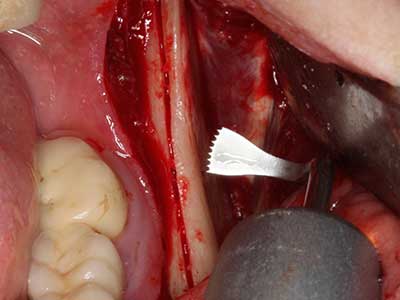

Piezo surgery has additional advantages when harvesting bone blocks. In addition to the high precision with osteotomy described above, the use of the thin saw tips specifically minimizes loss of material. Greater loss of material during harvesting can be expected with the thicker instrument tips, particularly when using Lindemann drills (Lakshmiganthan, Gokulanathan et al. 2012). The basal separation, which is necessary particularly for retromolar block transplants, is simplified by specially designed rectangular saws, with the result that piezo surgery is viewed as a precise, simple and safe procedure for harvesting retromolar bone blocks (Happe 2007) (Fig. 1-12).

When surgical procedures are performed on bone in the immediate vicinity of sensitive structures such as blood vessels or nerves, rotary instruments pose a significant risk of iatrogenic injury. Piezoelectric devices can be helpful for preparation of bone covers and removal of hard tissue close to nerves, particularly for exposure of nerves after iatrogenic injury but also during nerve lateralization for resective and reconstructive procedures or implant placement (Fig. 17-20). Light contact between the piezotip and the nerve does not generally result in damage but proceeding incautiously with saw-like motions or attachments where a residual bone substrate remains may cause temporary or even permanent nerve damage. However, the risk of damage is considered to be substantially lower than when using saws or milling instruments (Pereira, Gealh et al. 2014).